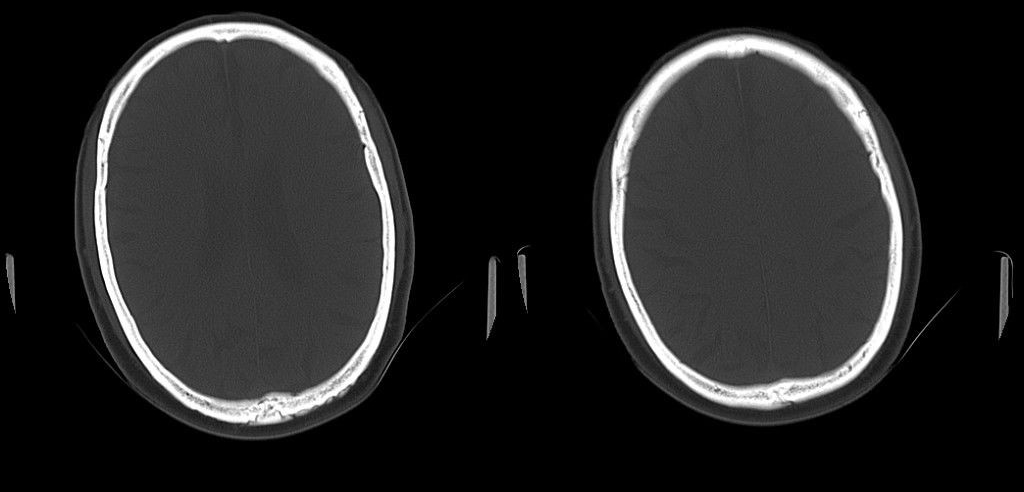

标题: CT25311:箭头所指是问题么?

该患者因头疼来诊,发现枕骨不规则缺损。

箭头所指为颅骨嗜酸性肉芽肿

蛛网膜颗粒压迹,讨论过很多了,年龄大了不考虑lch;脑白质疏松。

箭头所指:蛛网膜颗粒压迹。